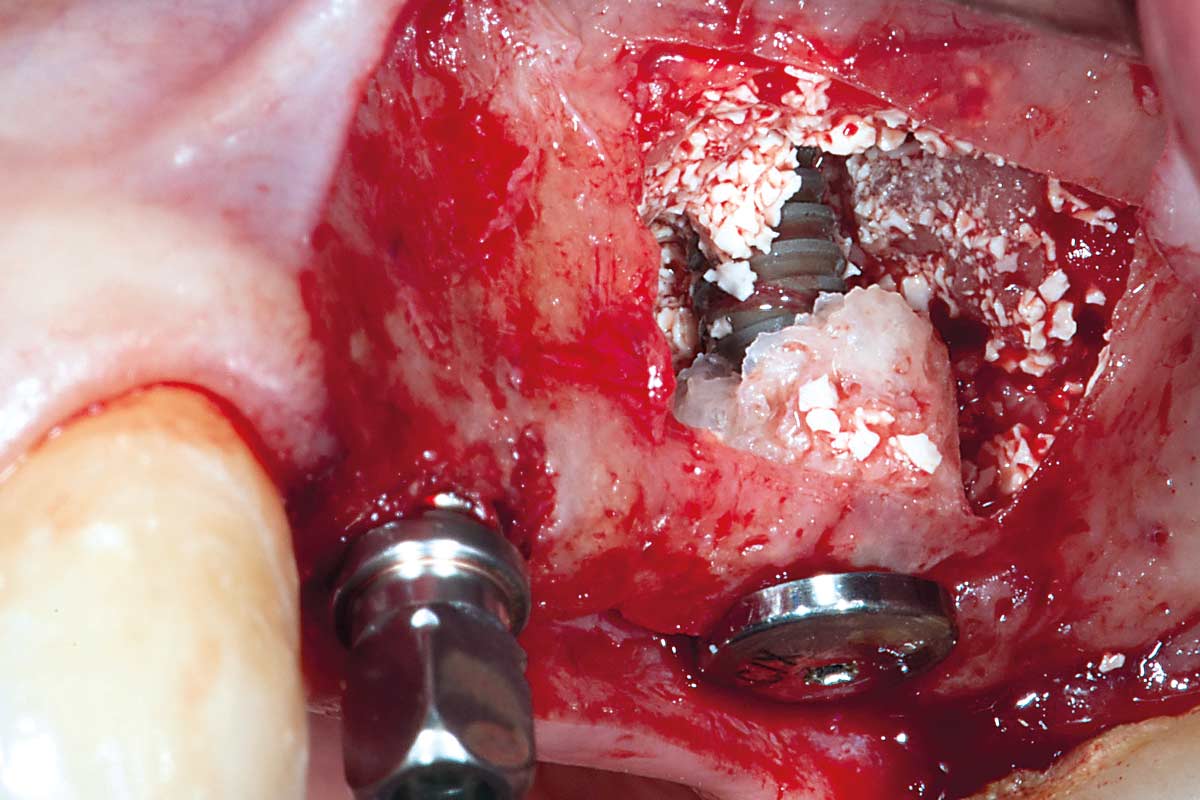

Sinus Floor Elevation with maxgraft® bonering - Dr. B. Giesenhagen

X-ray scan reveals initial situation with maxillary bone height in regio 15 of 1.5 mm